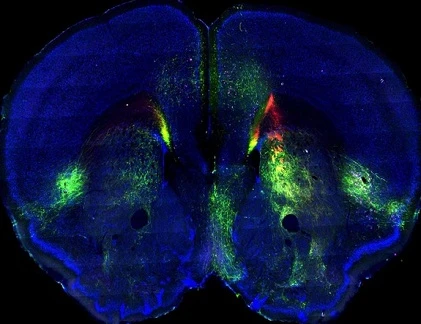

Não chuột đẹp. Hình ảnh mới của bộ não chuột là bản đồ toàn diện nhất về vỏ não động vật có vú. Sử dụng phép nội xạ huỳnh quang, các nhà nghiên cứu theo dõi kết nối giữa các vùng của vỏ não chuột, phía ngoài cùng, lớp nhăn của não.